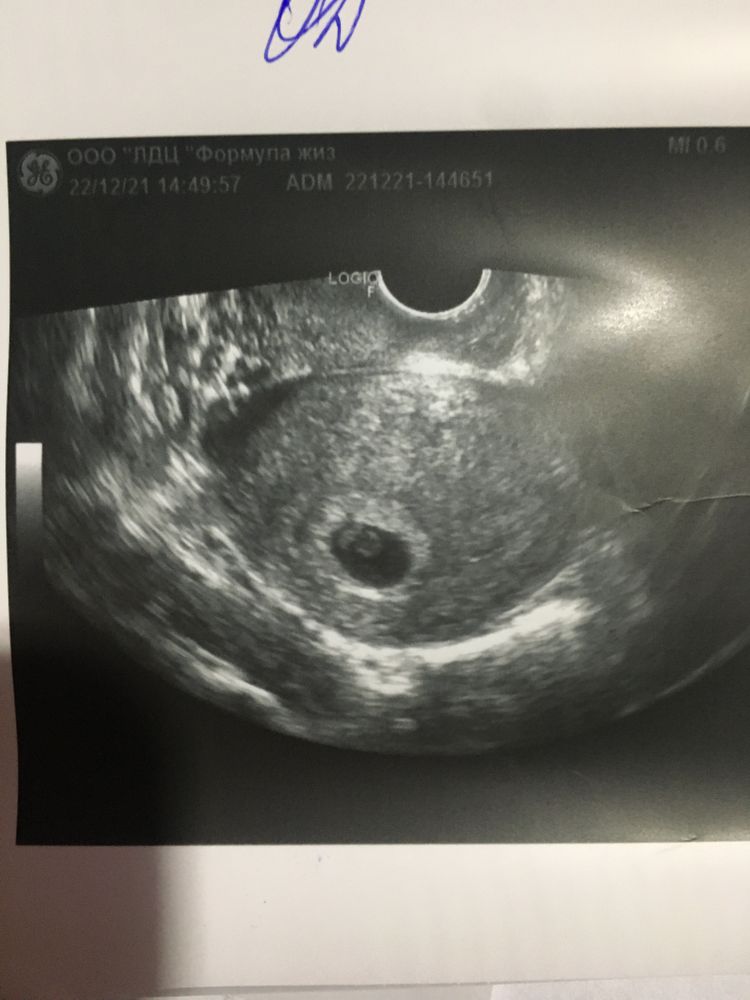

Первое узи в 7 недель